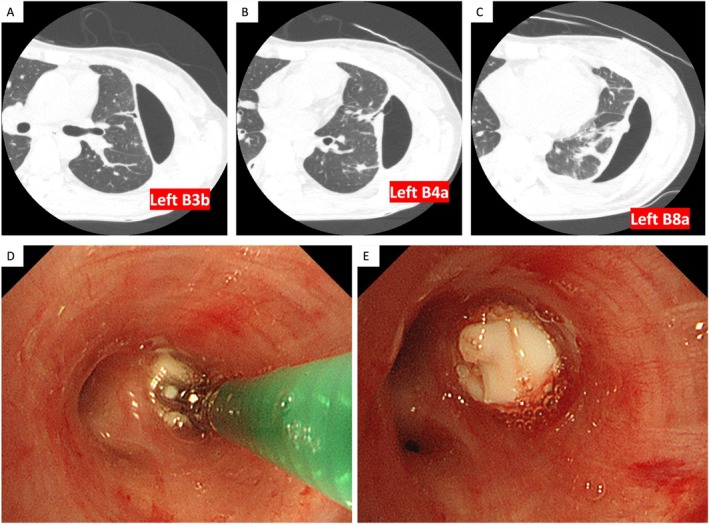

Lemierre's syndrome is a rare condition characterised by internal jugular vein thrombophlebitis and bacteremia caused by anaerobic organisms following an oropharyngeal infection. We report the case of a 29-year-old woman who presented with fever, sore throat, dyspnea, and chest pain. Chest computed tomography (CT) revealed lung suppuration, pneumothorax, and thrombosis of the left internal jugular vein, confirming the diagnosis of Lemierre's syndrome. During treatment, she developed pyothorax with bronchopleural fistulas and intractable pneumothorax. Although antibiotics and thoracic drainage controlled the infection, persistent air leakage and incomplete lung expansion remained. Placement of an endobronchial watanabe spigot (EWS) successfully resolved the air leak, allowing the patient to avoid surgery and be discharged. This case highlights the effectiveness of EWS in managing intractable pyopneumothorax secondary to Lemierre's syndrome.